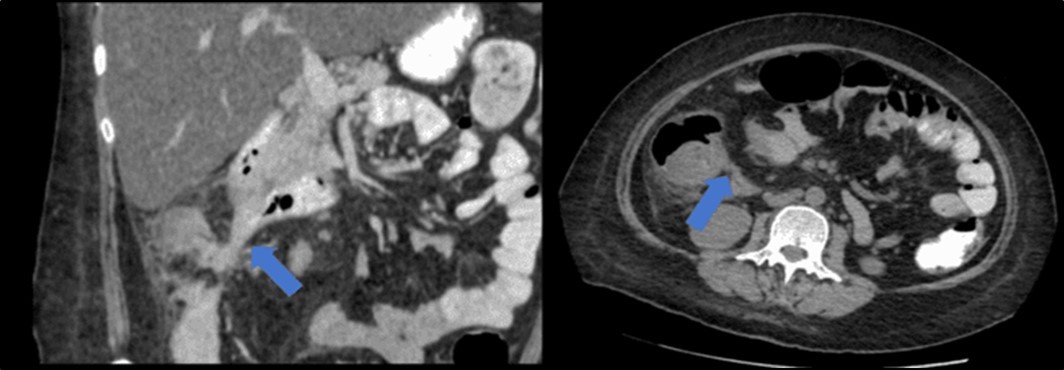

Figure 3.Coronal and axial view of the abdomen, the blue arrows pointing towards the suggestive communication to the ileum.

Coronal and axial view of the abdomen, the blue arrows pointing towards the suggestive                     communication to the ileum.

Figure 4.Coronal and axial view of the abdomen, the blue arrows pointing towards the suggestive communication to the duodenum

Coronal and axial view of the abdomen, the blue arrows pointing towards the suggestive             communication to the duodenum

There was no evidence of malignancy or IBD seen during both endoscopic procedures. Computed tomography (CT) scan of the whole abdomen was done which showed inflammatory changes involving the cecum and adjacent duodenum and ileum with coloenteric fistulae. There was noted progression of abdominal lymphadenopathies as well as ascites. Main consideration was an infectious disease process (i.e. TB) (Figure 2, Figure 3, Figure 4 to Figure 5).